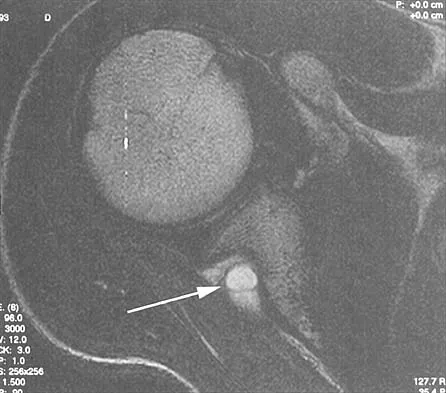

A coronal MRI scan through the shoulder joint is shown in Figure 26. The cyst indicated by the arrow will most likely cause compression of what nerve?

Explanation